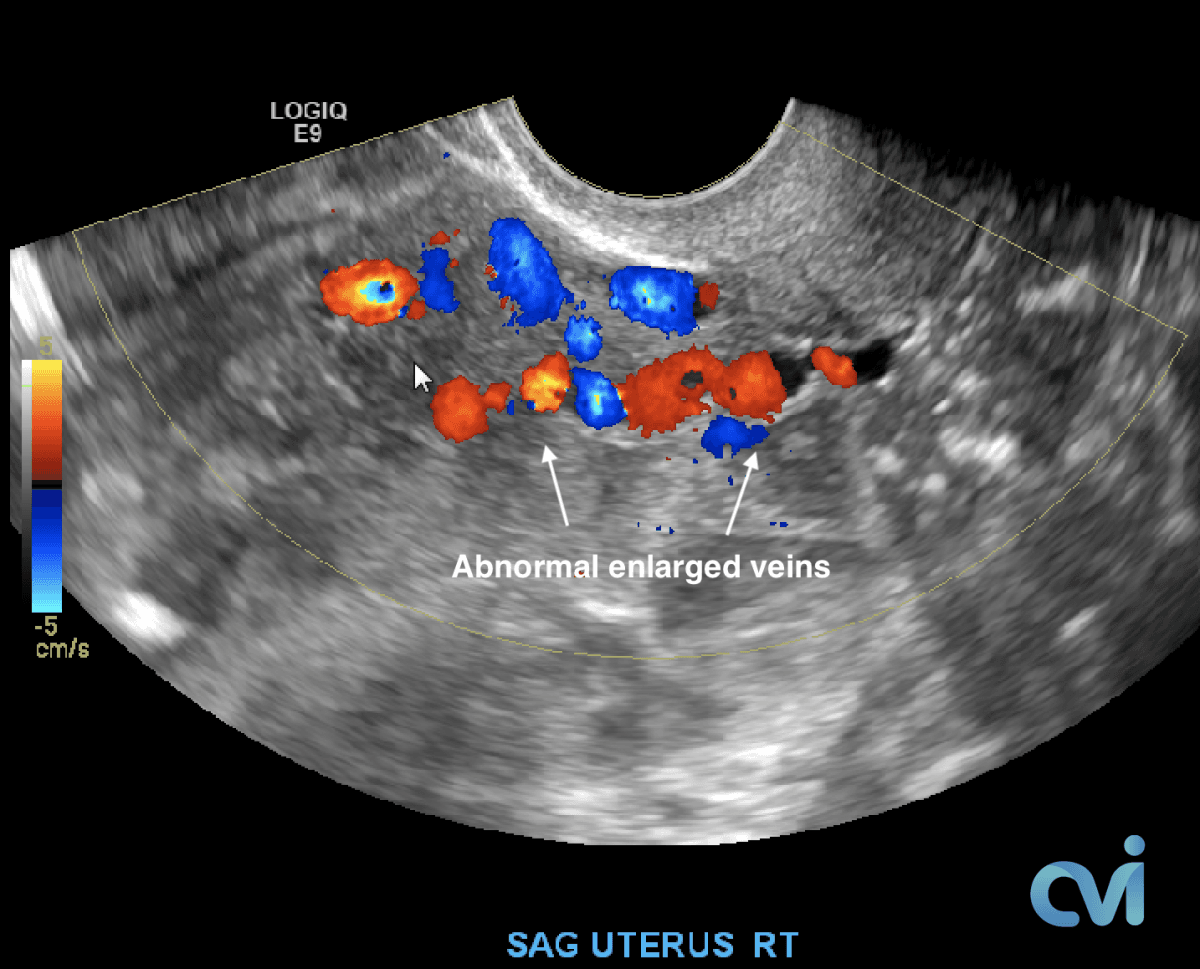

The abnormal veins dilate and cause varicose veins around the ovary and uterus because the valves don’t work properly. Blood flow is in the wrong direction, pooling in the veins and causing them to enlarge.

PCS can be diagnosed by Ultrasound or CT of the Abdomen and Pelvis.

Ultrasound examination is the least invasive study and can identify enlarged veins around the uterus and pelvis. However, sometimes the veins in the pelvis are difficult to see or can be missed if the technician is not specifically looking in the right area.

Magnetic resonance imaging (MRI) and computed tomography (CT) is another method to diagnose pelvic congestion syndrome. Our practice requires a CT of the Abdomen and Pelvis with contrast prior to treatment. This allows us to see where the varicose veins are coming from so that we can plan and do the appropriate treatment. Sometimes there are abnormal pelvic veins in addition to the ovarian veins that need treatment. Sometimes PCS can be missed on CT if the contrast injection is not timed appropriately or the vein is not directly measured.